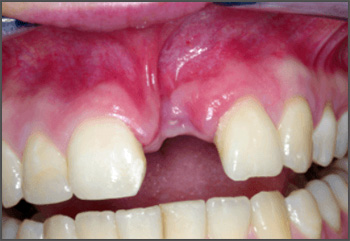

In early pregnancy, different parts of a babys face develop separately and then join together. If some parts do not join properly, the baby is born with a cleft.

A cleft lip and/or palate is the most common craniofacial abnormality, which is a problem to do with the skull and face.

A cleft lip can range from a little notch in the coloured part of the lip to a complete separation of the upper lip which can extend up and into the nose. This can affect one side of the mouth (unilateral) or both sides (bilateral), and can be complete (meaning the cleft goes up into the nose) or incomplete.

A cleft lip can also affect the gum where the teeth come through. Again, this can range from a small notch to a complete separation of the gum into two parts.

A cleft palate is a gap in the roof of the mouth. The back of the palate (towards the throat) is called the soft palate, and the front (towards the lips) is called the hard palate. A cleft can affect the soft palate or both the soft and hard palate.